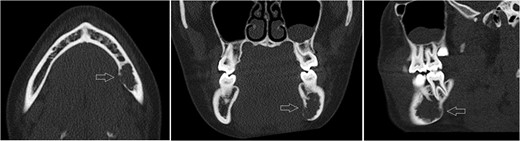

Likewise to panoramic X-ray, follow-up CT after 12 months showing no significant progression of the lesion.